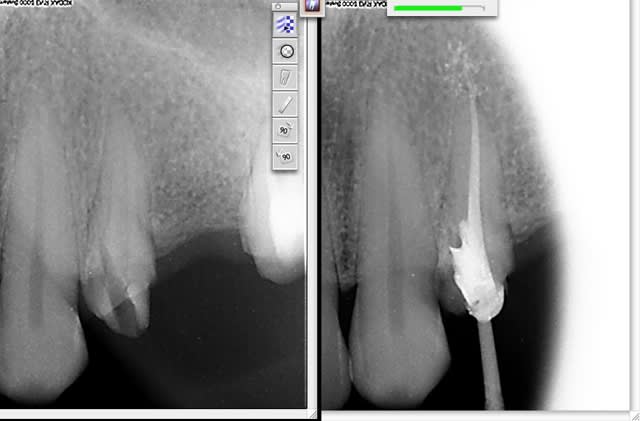

Je me suis un peu precipiter et me voici avec une perforation mésiale sur une 24 à environ 3,5mm du collet. Heureusement, j'ai réussi à recuperer l'axe et je vous presente la perf puis l'obturation canalaire qui a suivi.

avec les radios c'est mieux :)